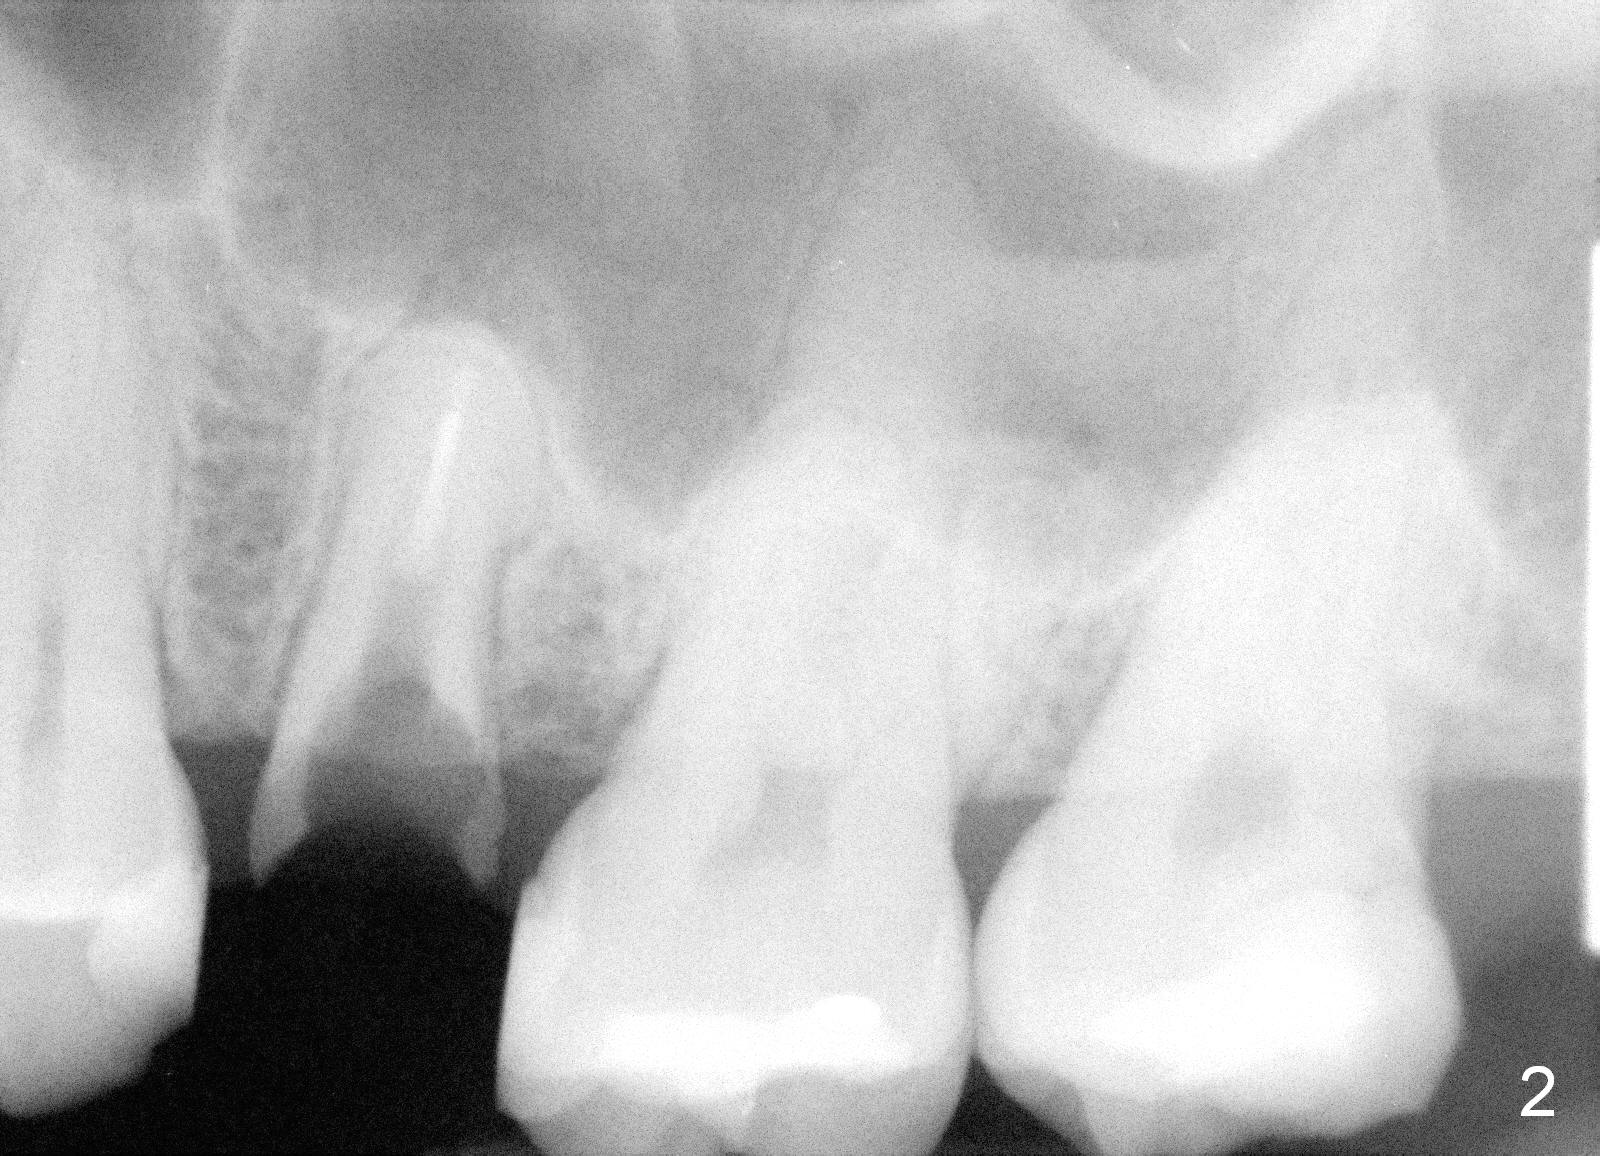

A 40-year-old lady has multiple restorations (Fig.1). The crown has dislodged from the tooth #13 twice in the last 2 years (Fig.2). When the tooth is extracted, a 4.5x10 mm bone level or 4.5x14 mm tissue level implant will be placed immediately with sinus lift (Fig.3).